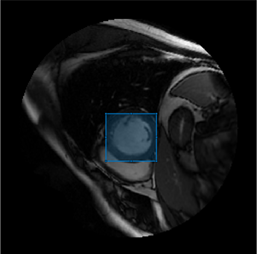

Overlay the detected object mask on the input image, and display the image with its object mask.

imMask = insertObjectMask(I,mask); imshow(imMask)